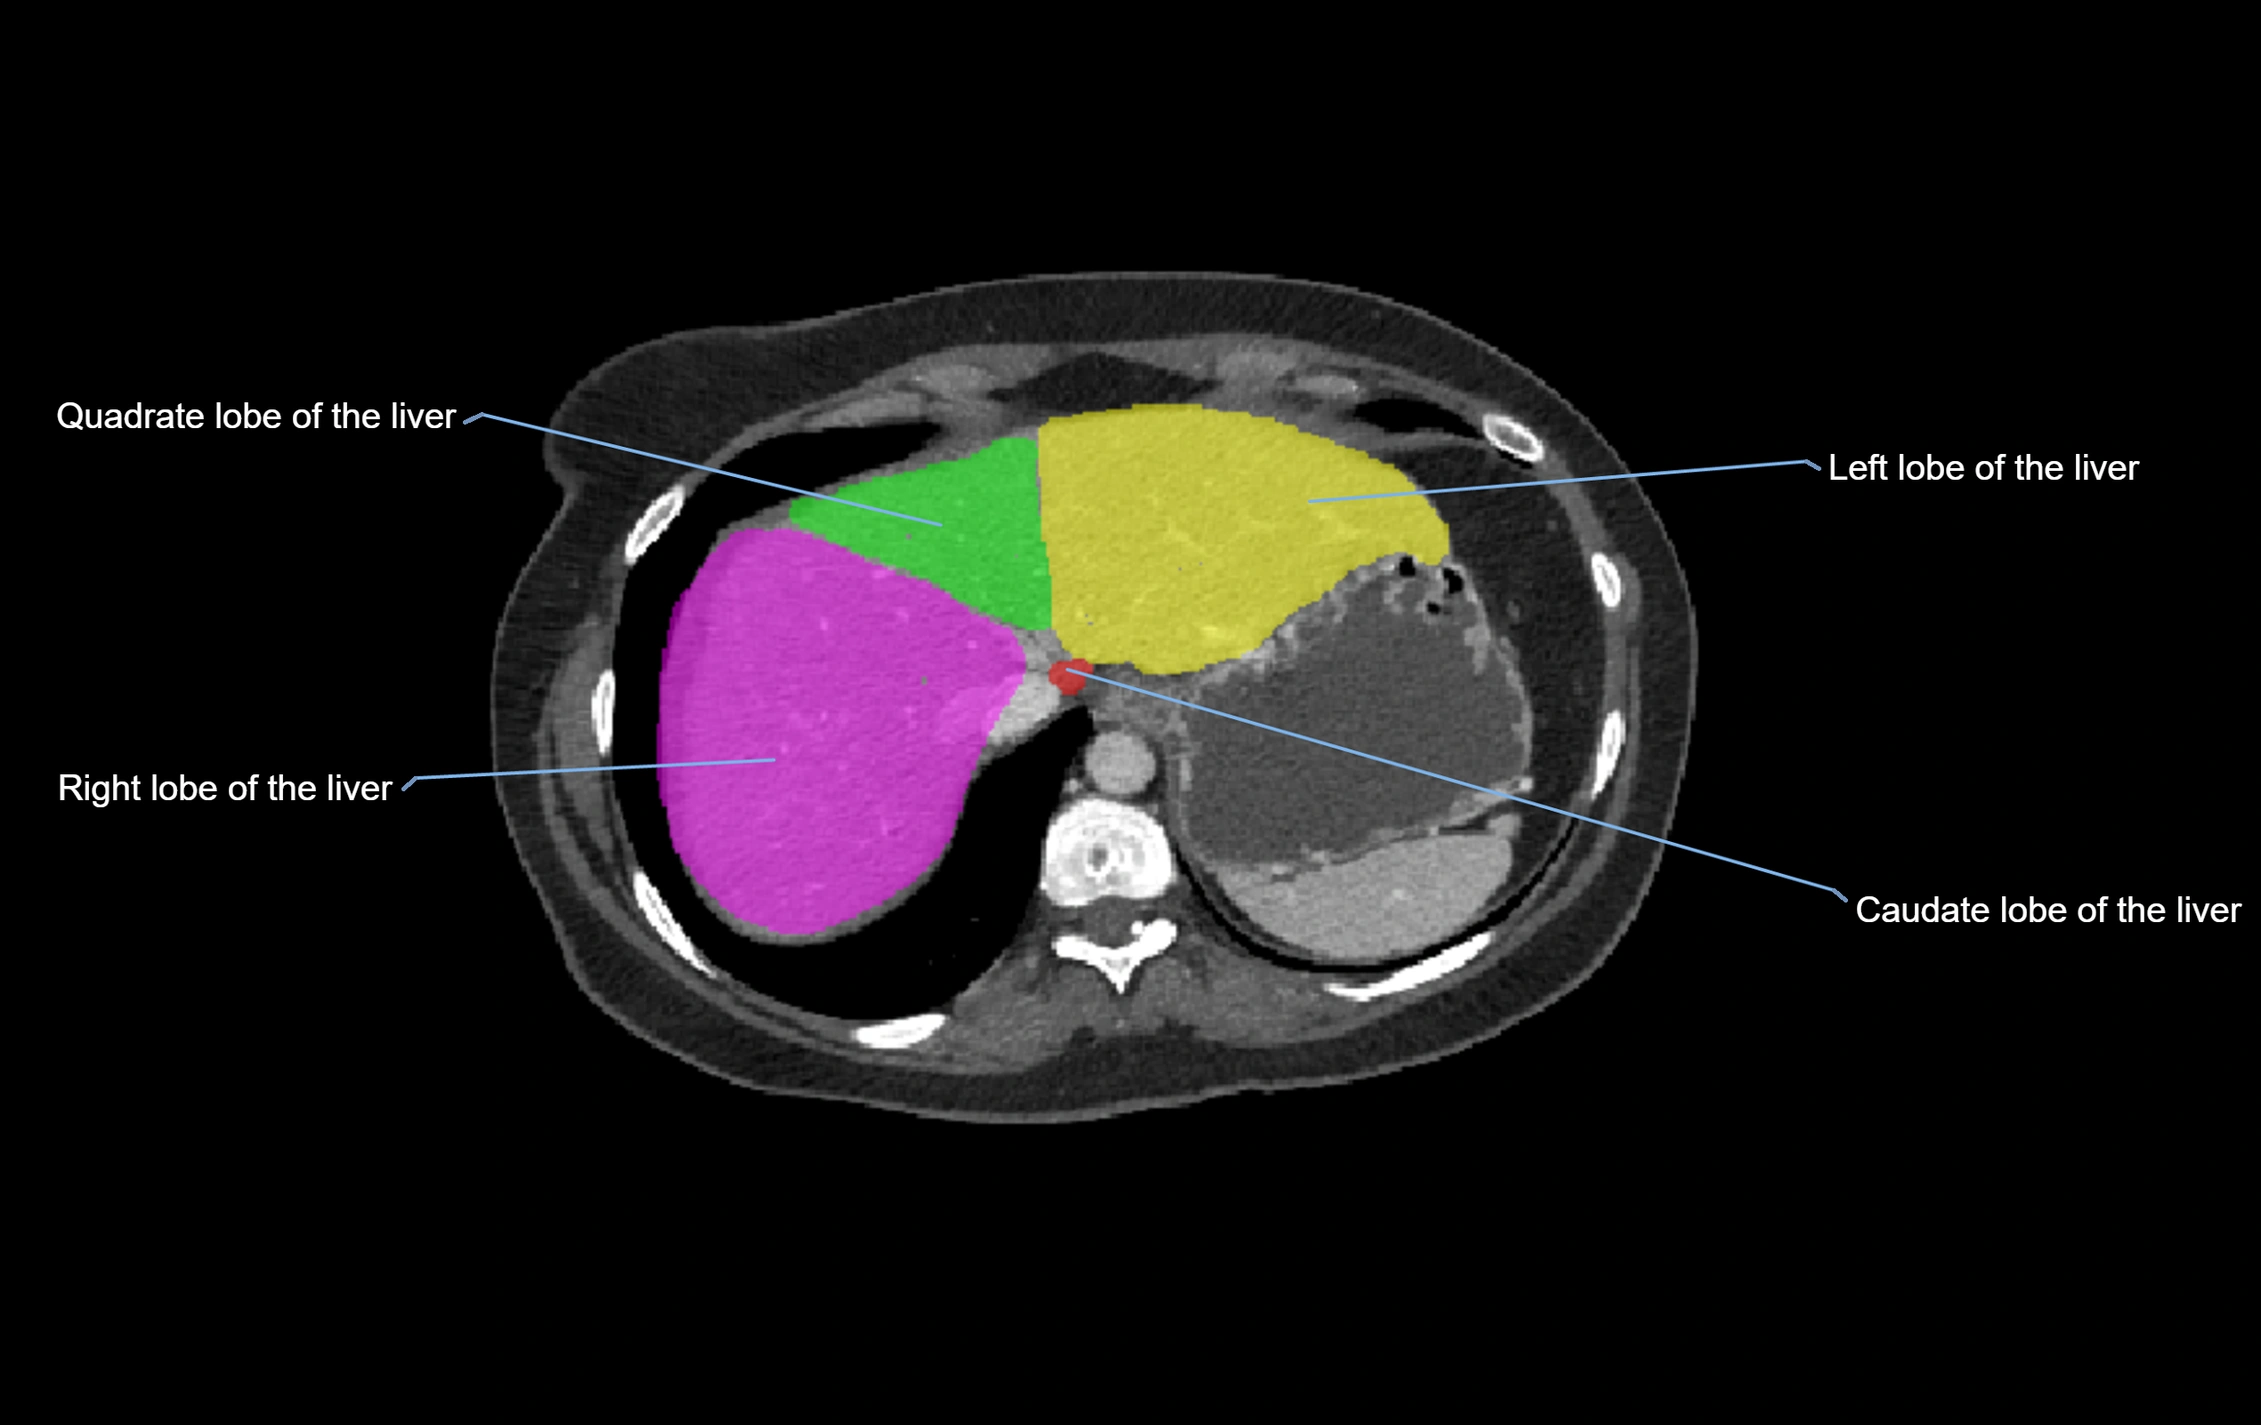

CT Appearance

CT Pre-Contrast:

• Caudate lobe appears as a soft-tissue density, isodense to the rest of the liver

• Enlargement may be appreciated in cirrhosis or Budd–Chiari syndrome

CT Post-Contrast:

• Homogeneous enhancement in the portal venous phase, similar to rest of liver

• Independent venous drainage into the IVC may be visualized

• Lesions follow characteristic CT enhancement patterns (HCC: arterial hyperenhancement with washout; hemangiomas: peripheral nodular enhancement with centripetal fill-in)

CT Venous Phase (functional significance):

• Caudate lobe often enhances relatively more than other lobes in Budd–Chiari syndrome, due to preserved venous outflow